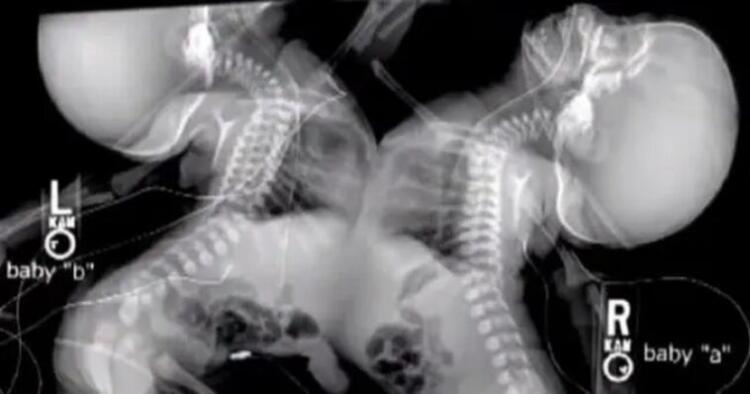

Τα δίδυμα ήταν ενωμένα στο στέρνο τους, στο διάφραγμα, στο συκώτι και στην μεμβράνη γύρω από την καρδιά. Ο φόβος ότι τα μικρά κορίτσια δεν θα επιβίωναν τον διαχωρισμό, οδήγησε τους γιατρούς να συμβουλέψουν την Shellie να τερματίσει την εγκυμοσύνη.

Σύμφωνα με το CNN, “Το συνολικό ποσοστό των ενωμένων διδύμων κυμαίνεται ανάμεσα στο 5% και στο 15%. Στο 75% αυτών των περιπτώσεων επιβιώνει μόνο το ένα παιδί, μετά από εγχείρηση.